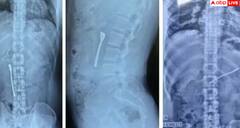

ਦਵਾਈ ਦੇ ਨਾਲ ਸਟੀਲ ਦਾ ਚਮਚਾ ਵੀ ਖਾ ਗਿਆ ਵਿਅਕਤੀ, ਜਾਣੋ ਕਿਵੇਂ ਡਾਕਟਰਾਂ ਨੇ ਕੱਢਿਆ ਬਾਹਰ?